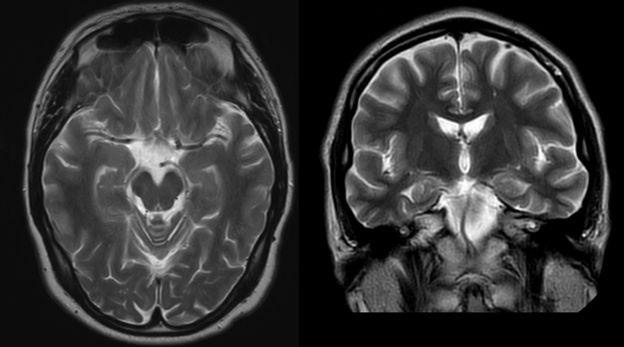

A Ressonância Magnética ao Crânio é um exame de imagem altamente preciso que permite avaliar o cérebro, meninges, vasos intracranianos e estruturas ósseas adjacentes. É um exame não invasivo, sem radiação, indicado em casos de sintomas neurológicos, lesões tumorais, alterações vasculares ou doenças inflamatórias do sistema nervoso central.

A Ressonância Magnética ao Crânio é um exame que utiliza campos magnéticos e ondas de radiofrequência para gerar imagens detalhadas do cérebro e estruturas circundantes. Por não utilizar radiação ionizante, é uma opção segura e eficaz no diagnóstico de patologias neurológicas, infecções, tumores, malformações vasculares e doenças desmielinizantes.